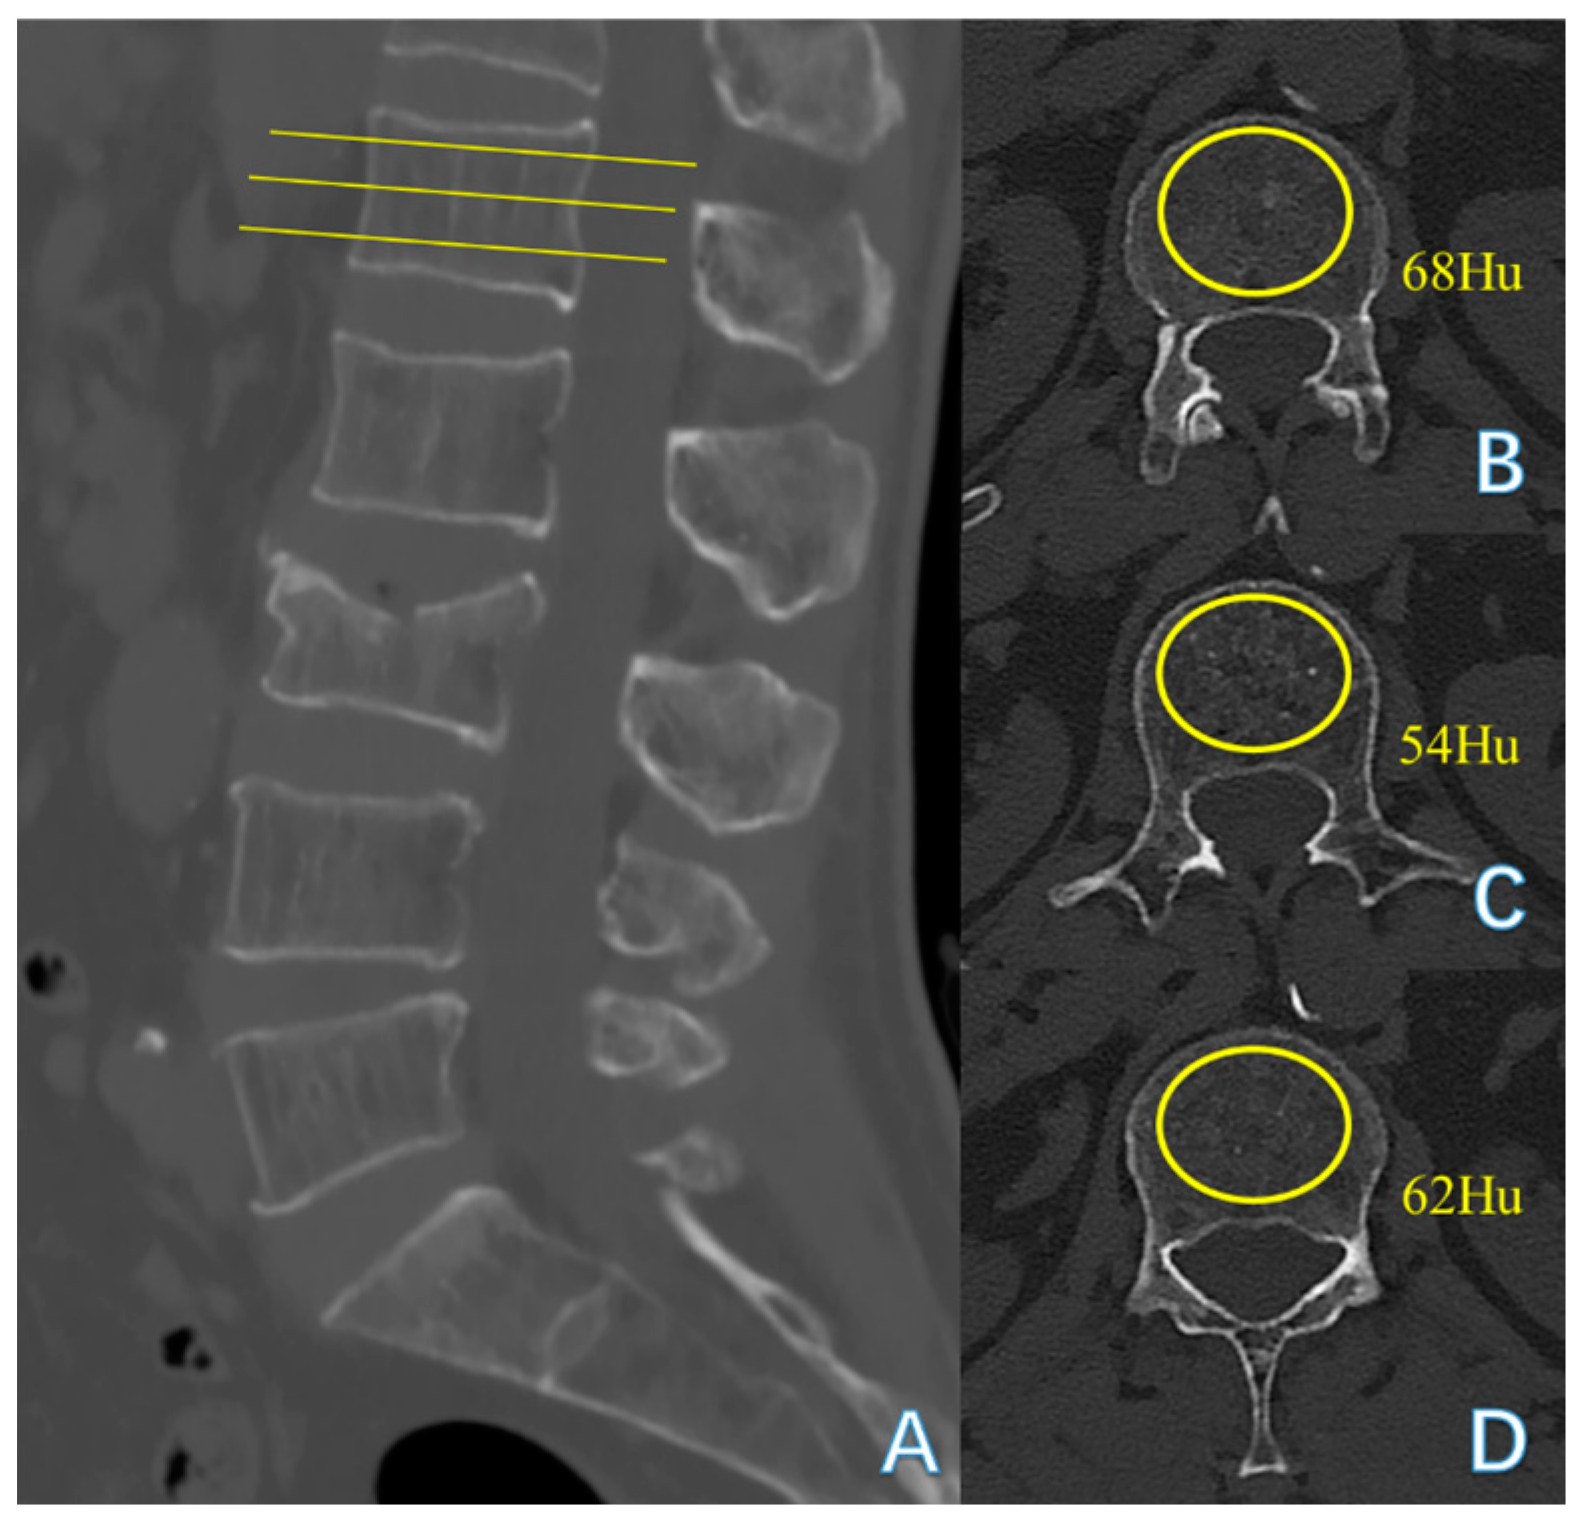

| Hu at upper lumbar levels | 83.000 (68.000, 100.000) | 66.000 (61.250, 80.250) | −3.110 | 0.002 * |